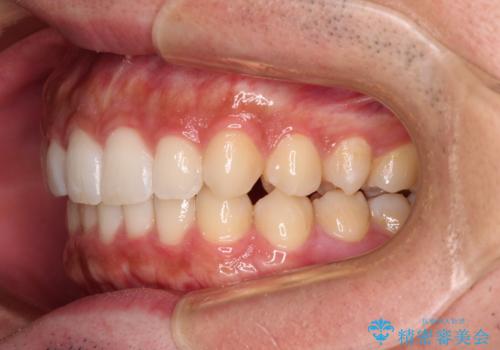

前歯のデコボコと突出感 インビザラインにて矯正治療

- 上下前歯のデコボコを気にして来院された患者様です。

インビザラインによる上下歯列の側方拡大と後方移動、IPR(歯と歯の間を削る)にるスペースの獲得により歯列を整えることとしました。

左上の小臼歯は捻転が強く、あえて180逆向きの状態で終了させる治療計画としました。

ご自宅と職場がともに遠方であったため、治療期間は長くなりましたが、患者様も我々も期待して以上に口元の突出感を改善することができました。